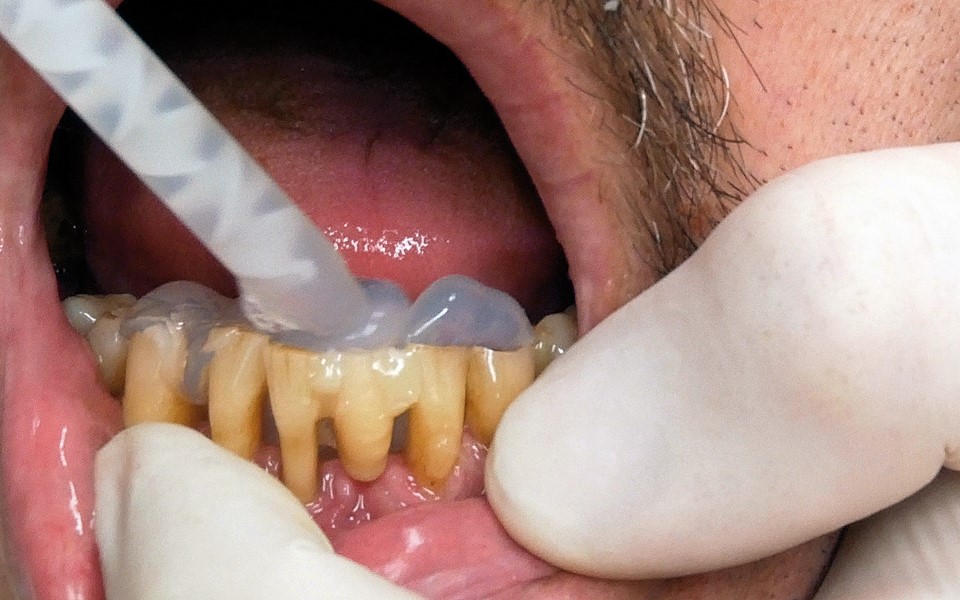

Jedną z popularniejszych metod stabilizacji zębów rozchwianych jest ich szynowanie. Metoda ta, wspierająca inne metody leczenia, jest powszechnie stosowana. Jednym z najnowocześniejszych materiałów wykorzystywanych w stomatologii do szynowania zębów jest taśma poliaramidowa. W opisanym przypadku autorzy pracy przedstawiają sposób uproszczenia całej procedury i ograniczenia ryzyka popełnienia błędu, szczególnie w sytuacji całkowitej utraty zęba. Uzyskano to dzięki zastosowaniu indeksu wykonanego z przezroczystego silikonu.

One of the more popular methods of stabilising loose teeth is to splint them. This method, aiding other methods of treatment, is generally used. One of the most modern materials used in dentistry for splinting teeth, is polyamide tape. In the case described the authors show how to simplify the whole procedure and limit the risk of making a mistake, particularly in the situation of total loss of one tooth. This was achieved thanks to the use of an index made out of transparent silicone.